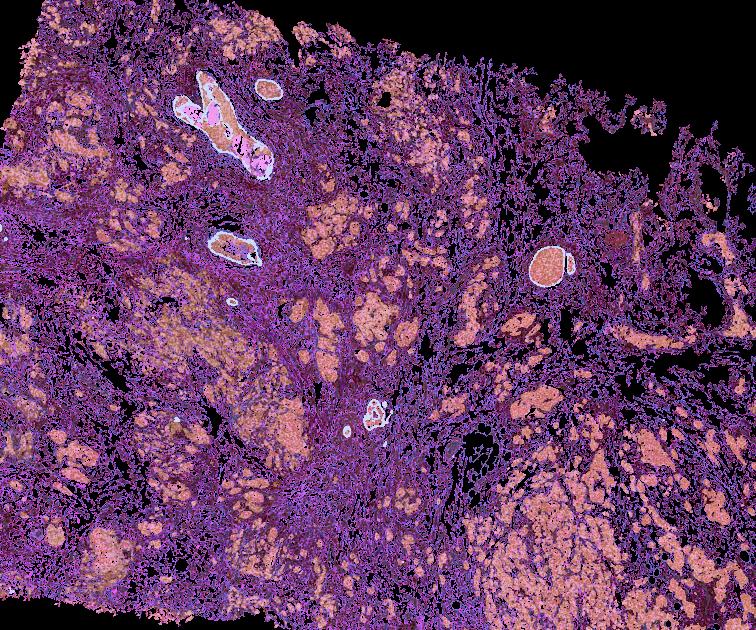

Atlas: Washington University

Breast cancer (BC) is defined by distinct molecular subtypes with different cells of origin. The transcriptional networks that characterize the subtype-specific tumor-normal lineages are not established. In this work, we applied bulk, single-cell and single-nucleus multi-omic techniques as well as spatial transcriptomics and multiplex imaging on 61 samples from 37 patients with BC to show characteristic links in gene expression and chromatin accessibility between BC subtypes and their putative cells of origin. Regulatory network analysis of transcription factors underscored the importance of BHLHE40 in luminal BC and luminal mature cells and KLF5 in basal-like tumors and luminal progenitor cells. Furthermore, we identify key genes defining the basal-like (SOX6 and KCNQ3) and luminal A/B (FAM155A and LRP1B) lineages. Exhausted CTLA4-expressing CD8+ T cells were enriched in basal-like BC, suggesting an altered means of immune dysfunction. These findings demonstrate analysis of paired transcription and chromatin accessibility at the single-cell level is a powerful tool for investigating cancer lineage and highlight transcriptional networks that define basal and luminal BC lineages.